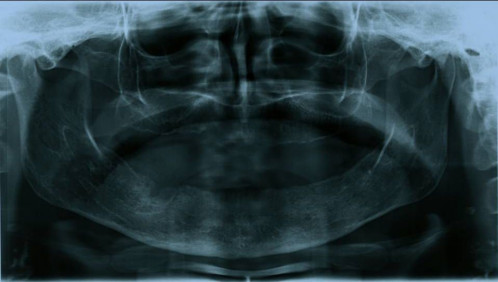

Makroskopie - intraoral präoperativ